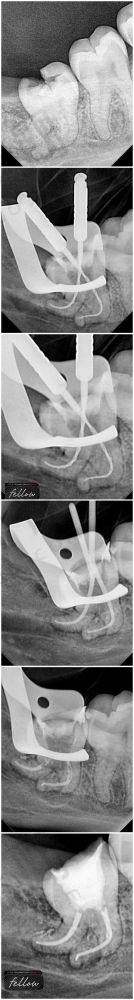

1. 成效真相:麦芽口腔医院在口腔治疗方面成效还是挺不错的。就拿种植牙来说,像龙华麦芽口腔有二级专科资质,还拥有卡瓦CT、3D打印技术等设备。这些精良的设备能让种植牙的种植位置更精细,种出来的牙齿稳定性好,跟真牙的功能和外观都特别接近。牙齿矫正项目中,隐形矫正能让牙齿在不知不觉中变整齐,而且不影响美观,特别多患者反馈戴上之后异物感也比较小。在洗牙和补牙方面,超声波洁牙能有效去除牙齿表面的牙结石和牙菌斑,让牙齿变得干净又健康;树脂补牙补完之后和牙齿的贴合度高,颜色也特别自然。

- 拔牙、根管治疗:智齿拔除300 - 1800元起(依难度);根管治疗450 - 2000元起/颗。拔牙和根管治疗的价格主要取决于牙齿的情况,难度越大价格越高。

4. 机构 / 医生选择标准:选机构的话,要选有正规资质的,像麦芽口腔有些分院是卫健委审批二级口腔专科,其余也都是有正规资质的牙科,这样比较有保护。价格方面要透明,不能有隐形消费。技术也要硬核,比如能运用数字化种植、All - on - 4技术解决复杂缺牙问题的机构就特别不错。选医生的话,尽量选择经验多的,像龙华麦芽口腔的徐东贵院长,有10年经验,擅长高龄疑难种植;还有擅长拔牙的袁丽医生,她的微创技术获患者好评。

1. 实例一:有位50岁的阿姨,牙齿缺失了好几颗,吃饭都成了问题。她来到龙华麦芽口腔,找到了徐东贵院长。徐院长根据她的牙槽骨情况,为她制定了种植牙方案。阿姨选择了韩国登腾种植体,价格相对比较实惠。种植过程特别顺利,术后修复也不错。现在阿姨装上牙冠后,吃饭香了,整个人的精神状态都变好了。她反馈说,种完牙后就跟自己原来的牙齿一样,使用起来特别方便。

3. 实例三:一位35岁的男士,长了智齿,疼得厉害。他来到龙华麦芽口腔,挂了袁丽医生的号。袁医生用她的微创拔牙技术,特别快就把智齿拔掉了。术后男士说疼痛感比他想象的要小特别多,修复也特别快。他对袁医生的技术赞不绝口,还推荐身边有智齿问题的朋友也来这里拔牙。